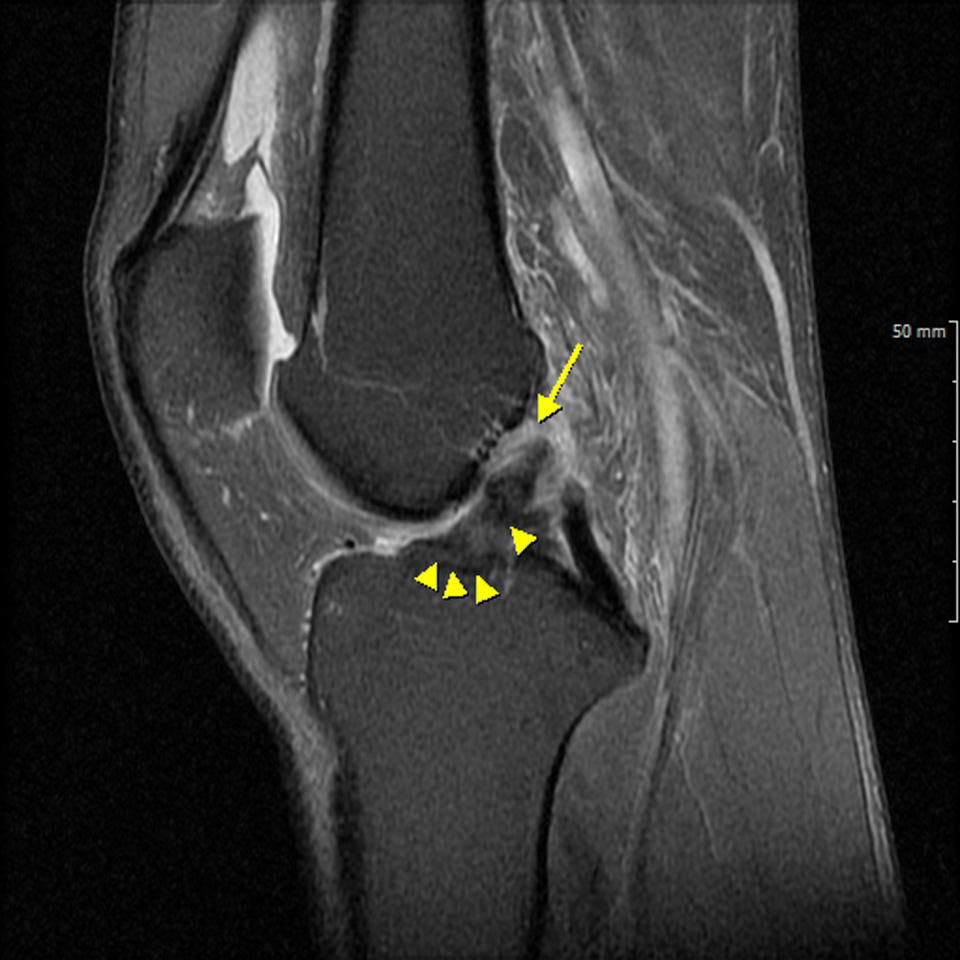

무릎의 MRI 영상에서 엑스레이에서는 안보이는 연골 손상 부분을 확인할 수 있다.

- 환자 동의하에 게시된 이미지입니다.